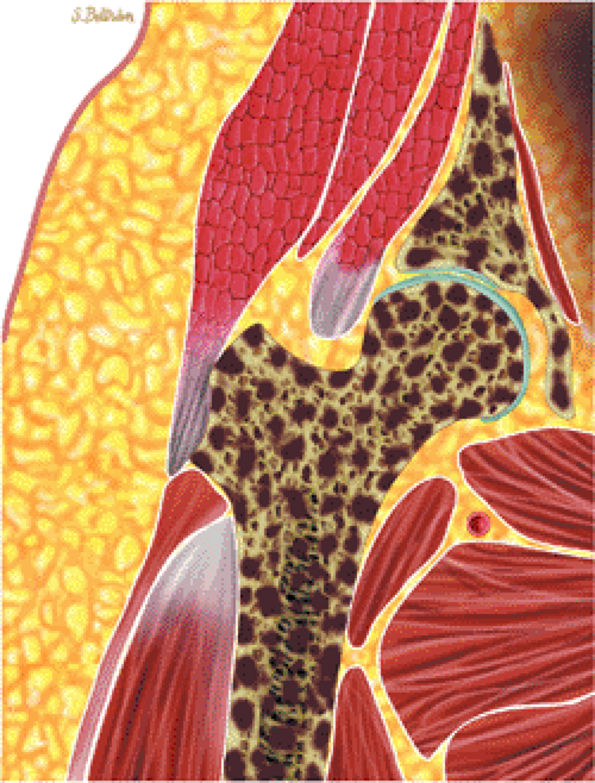

FIGURE 13.60 ● Coronal graphic illustration of the hip shows diffuse metastatic marrow replacement. The pelvic bones are a common site for metastatic disease due to their rich vascular supply.

|